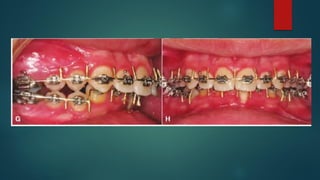

conditions required surgical correction to improve the airway. D, Frontal view with smile

and intra oral views with orthodontic decompensation in progress.